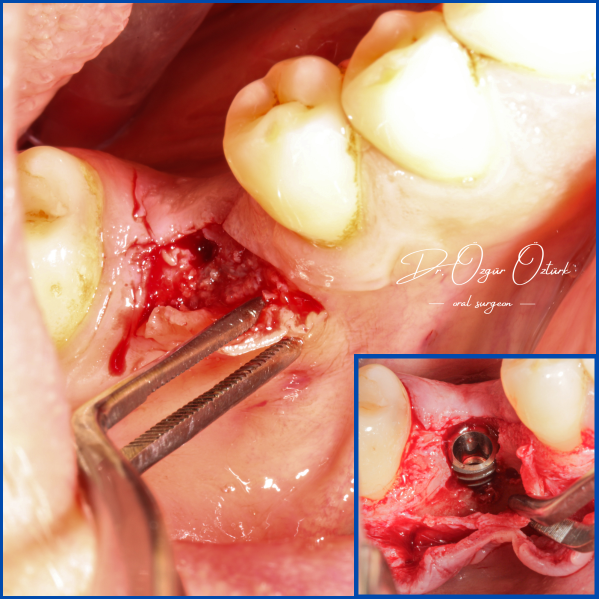

Kist nedeni ile çene kemiğinde defekt oluşmuş vakamıza sert ve yumuşak doku ogmentasyonu uyguladık.